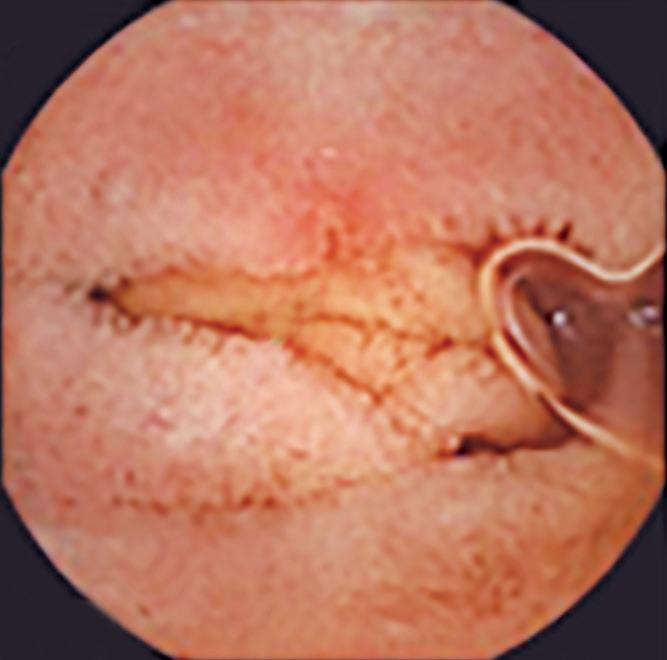

La endoscopía continúa siendo la piedra angular en la evaluación esofágica debido a su capacidad para excluir malignidad, identificar la enfermedad mucosa y detectar una obstrucción mecánica. Sin embargo, hasta el 50 - 70% de los pacientes sometidos a una endoscopía digestiva alta por síntomas esofágicos no presentan anormalidades evidentes, lo que deja a los clínicos con escasa claridad diagnóstica y a los pacientes con síntomas persistentes.3 En estos casos son necesarias las pruebas funcionales esofágicas -manometría de alta resolución (MAR), monitoreo ambulatorio del reflujo y esofagograma baritado- para establecer un diagnóstico. Lamentablemente, estos estudios suelen realizarse semanas o meses más tarde, requieren derivación a centros especializados y están limitadas por una tolerancia subóptima y una proporción no despreciable de estudios incompletos.2, 3

En primer lugar, la endoscopía proporciona información anatómica y mucosa crítica que contextualiza los hallazgos fisiológicos. La graduación de la esofagitis mediante la clasificación de Los Ángeles, la evaluación de EoE con biopsias sistemáticas y puntuación EREFS, la valoración de la válvula gastroesofágica y de la hernia hiatal, así como la identificación de signos endoscópicos sugestivos de acalasia, aportan elementos fundamentales para la interpretación integrada de los datos fisiológicos posteriores.8

En segundo lugar, la introducción de herramientas estructuradas de estratificación endoscópica de riesgo, como el Clinical Achalasia Risk Score (CARS), permite estimar la probabilidad de acalasia basándose en hallazgos endoscópicos reproducibles. El CARS incorpora la evaluación del contenido esofágico, la anatomía luminal, la resistencia a nivel de la UEG y los cambios mucosos relacionados con estasis, demostrando un excelente valor predictivo para acalasia cuando los puntajes superan los umbrales predefinidos.4, 5